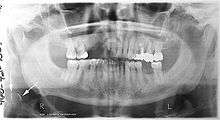

OPTs are used by health care professionals to provide information on:

- Impacted wisdom teeth diagnosis and treatment planning - the most common use is to determine the status of wisdom teeth and trauma to the jaws.

- Periodontal bone loss and periapical involvement.

- Finding the source of dental pain

- Assessment for the placement of dental implants

- Orthodontic assessment. pre and post operative

- Diagnosis of developmental anomalies such as cherubism, cleido cranial dysplasia

- Carcinoma in relation to the jaws

- Temporomandibular joint dysfunctions and ankylosis.

- Diagnosis of osteosarcoma, ameloblastoma, renal osteodystrophy affecting jaws and hypophosphatemia.

- Diagnosis, and pre- and post-surgical assessment of oral and maxillofacial trauma, e.g. dentoalveolar fractures and mandibular fractures.

- Salivary stones (Sialolithiasis).

- Other diagnostic and treatment applications.[1]